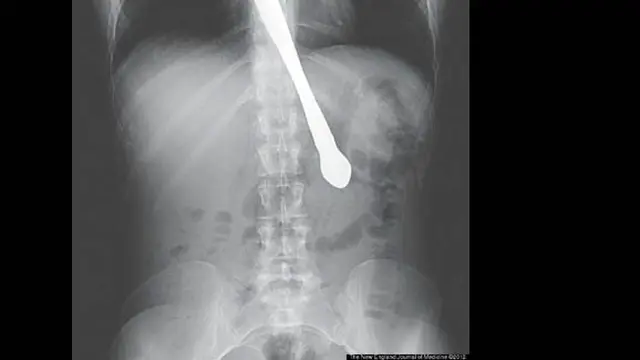

Penderita Bulimia Telan Pisau

Pernah mendengar gangguan bulimia? Gangguan makan ini akan membuat pelakunya memuntahkan kembali makanan mereka dengan sengaja. Biasanya mereka memancing keluarnya makanan dengan bantuan jari yang didesak pada tenggorokan. Bisa juga dengan bantuan benda lain, misalnya pisau.

Wanita 30 tahun ini dari Atlanta, punya riwayat bulimia. Dia ingin menunjukkan bahwa dirinya tidak lagi memuntahkan makanan dengan memamerkan hal itu pada teman-temannya. Wanita ini memancing dengan pisau di tenggorokan. Sayangnya, pisau itu justru tertelan. Kejadian ini bahkan ditulis dalam New England Journal of Medicine.